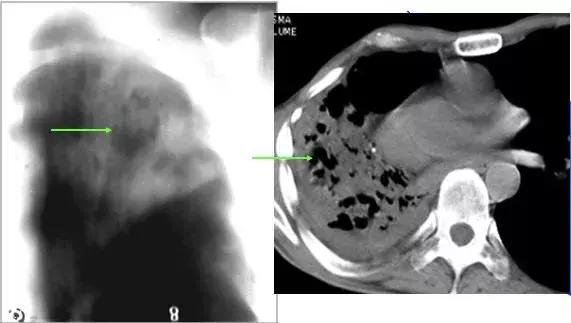

CT征象九:空气新月征

肺内空洞或空腔内的球形病灶与洞壁之间形成的新月形透亮影称为“空气新月征”。

空气新月征曾认为是曲霉菌球的特异征象,特点是随着体位的变动,空洞或空腔内的霉菌球可移动,但始终位于近地位。也可见于其他疾病(其内球形病灶可能不移动)

仰卧与俯卧位CT扫描,霉菌球始终处于近地位,空气新月征位于上方

同影异病:案例

“空气新月征”也可见于肺结核病例,常伴有钙化,多不随体位而变动